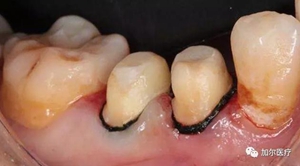

最近刷牙發(fā)現(xiàn),牙齒邊緣接近根部有黑黑的一圈,如果是蛀牙從外表足以看清,可是在牙齦內(nèi)你根本不知道,其實是因為戴了烤瓷牙冠的緣故,那也不至于牙齦變黑吧,這黑黑的東西究竟哪來的?

問題就出在烤瓷牙內(nèi)冠材料,生物相容度低,劣質(zhì)的金屬成分游離到牙齦邊緣,長期沉淀導(dǎo)致發(fā)黑,外表是清理不掉,另外還有一種是醫(yī)生技術(shù)不當(dāng)所致,牙冠和牙齦出現(xiàn)縫隙,殘渣和細(xì)菌容易進入冠內(nèi)滋生,感染原牙使之齲壞變黑,這樣連烤瓷牙

都得重新做。